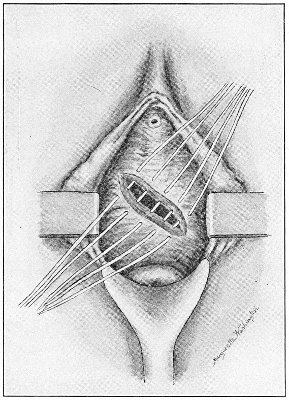

The secondary operation is performed at any time after cicatrization has occurred—often many years after the receipt of the injury. This operation is at present one of the commonest in gynecology, because the injury is not detected, is neglected, or is improperly repaired after labor. In the secondary operation an anesthetic is necessary. The mucous membrane must be removed or denuded on the posterior wall and about the mouth of the vagina, in order that the lacerated structures may be brought again in apposition. The denudation is best made by means of scissors curved on the flat (Figs. 24 and 25).

The strip of mucous membrane to be removed is picked up with a tenaculum (Fig. 26) or with tissue forceps 65 (Fig. 27); the scissors are placed with the blades parallel to the surface to be denuded, and the strip is cut away evenly, in one piece if possible. A similar contiguous strip is removed, and so on until the necessary surface is bare. Sponges in holders (Fig. 28) or continuous irrigation may be used to remove blood.

For all operations on the perineum round-pointed needles curved at the tip should be used (Fig. 29). The tissues are always sufficiently soft for the passage of such a needle. A needle with a cutting edge is unnecessary and may increase the bleeding.

The needle may be held in any kind of needle-holder preferred. The Emmet needle-holder (Fig. 30) is very convenient.

The point of the needle should be guided and held by the tenaculum. The tenaculum must always be held in a plane parallel with the plane of the needle-holder; otherwise the needle-point may escape from the embrace of the tenaculum. 66

Silver wire and silkworm gut are the best sutures in the operation of perineorrhaphy.

The suture is conveniently attached to the needle by means of a silk carrier (Fig. 31).

The sutures may be fastened by passing the ends through a perforated shot which is slipped down to the line of union and compressed by the shot-compressor (Fig. 32). All blood should be carefully removed from the surfaces that are brought together. The sutures should only be sufficiently tense to produce accurate apposition. A light gauze drain should be introduced in the vagina, and should be removed in forty-eight hours. Afterward one vaginal douche of about a quart of warm bichloride solution (1:2000) should be administered every day. After the douche the labia should be separated and the vagina carefully dried by cotton held in dressing-forceps. Except in those cases in which the sphincter ani is involved, the bowels may be moved on the second or third day. The woman should stay in bed for two weeks, at the end of which time the sutures should be removed. 67 She should avoid heavy lifting, long standing, and bicycle- or horseback-riding for two months after the operation. Constipation should always be avoided. Coitus may be resumed six weeks after operation.

Slight Median laceration of the Perineum.—In this injury the tear takes place through the fourchette. Posteriorly it may extend as far as the sphincter ani muscle. Upward it may extend for an inch up the posterior vaginal wall. The appearance of this tear is shown in Fig. 33. It will be noted that, as this tear takes place in the median line, none of the muscles that support the perineum are involved, nor are the planes of fascia injured. The perineum is slightly split, and the insertions and origins of the muscles and the fascia are slightly separated. The supporting structures of the perineum and the pelvic floor are, however, uninjured.

Fig. 33.—Recent slight median laceration of the perineum: sutures introduced.

If this tear is detected after labor, it should be closed by the immediate operation. A slight tear involving chiefly the cutaneous aspect of the perineum should be closed by three or four sutures introduced from the outside, as in Fig. 33. The needle should be introduced about a quarter of an inch from the edge of the wound. It should not be passed parallel with the plane of the lacerated surface, but should be swept outward and then inward toward the 68 angle at the bottom of the tear (Fig. 34). It may either emerge at the angle and be re-introduced, or it may be passed directly through to the skin-margin on the opposite side of the wound. If the suture is passed in this way, there will be perfect apposition throughout the whole surface of laceration. If the sutures are improperly passed, there may result only apposition of the skin-edges.

Fig. 34.—Diagram representing the correct and the incorrect method of passing the suture for closure of slight perineal laceration.

If the laceration extends up the posterior vaginal wall, two sets of sutures must be introduced—one on the vaginal aspect of the tear, and one on the skin aspect (Fig. 35).